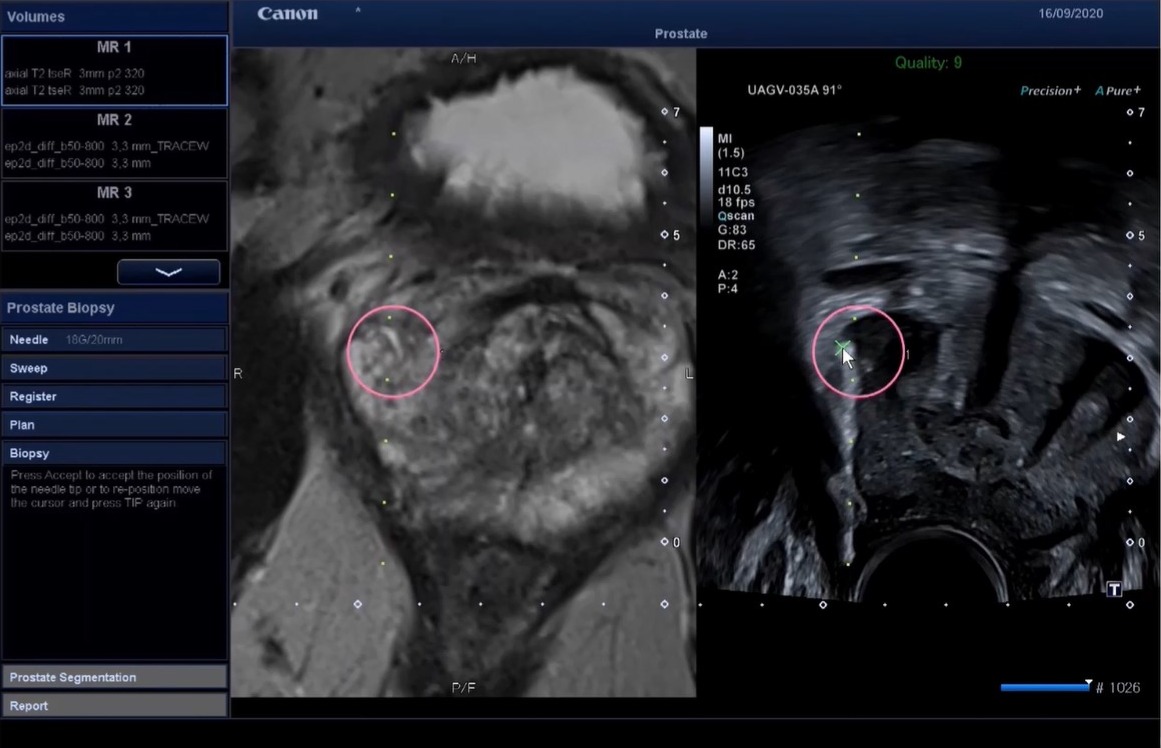

Bei Verdacht auf eine

bösartige Prostataerkrankung können wir mit unserer hochmodernen

Gewebeentnahmetechnik (Fusion der MRT-Aufnahmen mit den

Live-Ultraschallbildern) äußerst gezielt Gewebeproben entnehmen.

Bei Verdacht auf einen bösartigen Prostatatumor wird im ersten Schritt in einem radiologischen Institut eine MRT-Untersuchung der Prostata durchgeführt. Zeigen sich dort verdächtige Areale, wird im zweiten Schritt durch eine Fusionsbiopsie Prostatagewebe zur feingeweblichen Untersuchung entnommen. Die dabei durch uns angewandte hochmoderne Technik, bei der die MRT-Bilder über die Live-Ultraschallbilder gelegt werden, ermöglicht eine gezielte Entnahme von Gewebe aus dem definierten betroffenen Verdachtsherd.